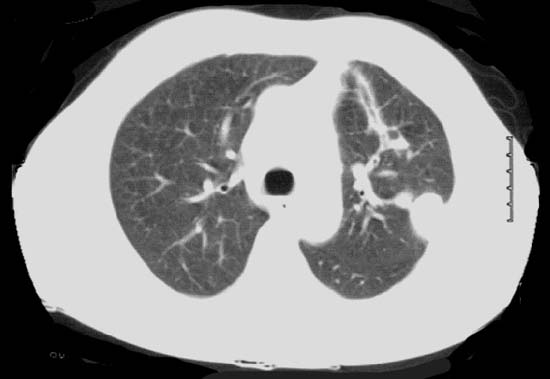

When an isolated pulmonary nodule is lying deep to a flat surface of the lung, VATS wedge resection using the conventional endoscopic staple-cutter is often technically difficult. Even if this could be done, it usually sacrifices more functional lung tissue than would be necessary or desirable. This could have a major impact on the recovery of patients who are elderly, frail with multiple co-morbidities, and borderline lung function. It is for this group of patients that new technological approaches may offer an advantage. Patients with peripheral pulmonary nodules for diagnostic or therapeutic wedge resection are suitable candidates to consider. The nodule should ideally be located in the peripheral one-third of the lung, and should be less than 3cm in maximal diameter (Figure 1).